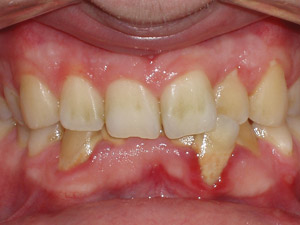

Figure 3

Sandra is a common example of a patient having a malocclusion that is the direct cause of her recession, and abfractions. When we first examined Sandra, her chief complaint was her smile (see Figure 3). She was unhappy with her smile and "crooked" teeth and had the desire to fix them.

Sandra expressed to us that she looked into clear aligner therapy but was told she was not a candidate. She was told she would need two years in braces and possibly some teeth extracted. These treatment options were undesirable, so she chose to do nothing. We assured her that she was an excellent candidate for clear aligner therapy, and her treatment time would be 14 months with no extractions.

At the consultation, Sandra's photos were used to teach. The photo of the lower crowding with the lingual plaque and calculus was used to teach Sandra the difference between crowded teeth and aligned teeth. We also informed her that her teeth are not actually "crooked" (her chief complaint). The mandibular occlusal view pointed out her V-shaped arch provided no room for her teeth to fit within the arch.

The remaining photos were used to teach the difference between a good bite and a bad bite. Sandra learned about clefting, recession, abfractions, and the visible areas of enamel wear on multiple teeth. Sandra understood that clear aligner therapy would change her bad bite to a good bite, resulting in a beautiful, healthy smile. My goal went further than that. I knew the benefits of aligned teeth include increased longevity, a healthy periodontium, and proper occlusion for her to enjoy a lifetime of oral health.

Sandra was excited to begin treatment. So her case was submitted, developed, and delivered in short order. Her treatment involved 24 aligners, which took exactly 12 months of treatment time.

Upon completion of treatment, she had a healthy, stable, and functional occlusion. Notice the clefting, recession, and abfraction improvements in the photographs related to her case. This validates my objection to the current standard of care of "waiting and watching" for conditions to worsen. Instead, my hygienists and I educate patients on the long-term solutions of clear aligner therapy so they can make educated choices regarding their oral health.